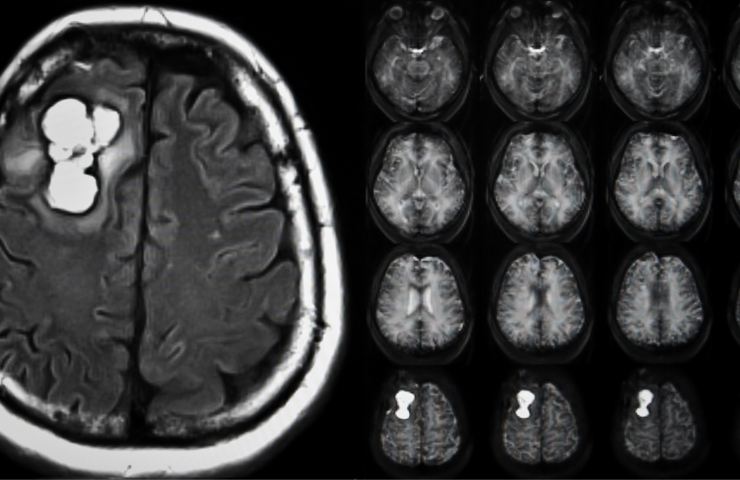

I risultati di un esperimento condotto in merito alla cura dei tumori porta all’emergere di una scoperta potenzialmente molto, molto importante per il futuro.

Ovvero in che modo i nutrienti estrapolati da alimenti sani riescano ad intervenire su processi fisiologici di vario tipo, anche quelli che riguardano il dovere affrontare il sorgere di forme tumorali. Lo studio in questione, pubblicato sulla rivista di settore Nature, hanno posto l’accento sul ruolo del TVA, l’acido trans-vaccenico che può migliorare il lavoro di specifiche cellule, le T CD8+ nell’individuare ed eliminare le cellule del tumore che sono malate.

In seguito ad esperimenti su cavie di laboratorio, la dieta con molto acido trans-vaccenico TVA che è stata loro sottoposta è riuscita in effetti ad abbassare il rischio di contrarre dei tumori. Le cellule responsabili di neoplasie e melanomi risultavano contrastate ed il loro lavoro malevolo stoppato. Con le cellule sopracitate, le T CD8+, capaci di penetrare i tumori con efficacia.